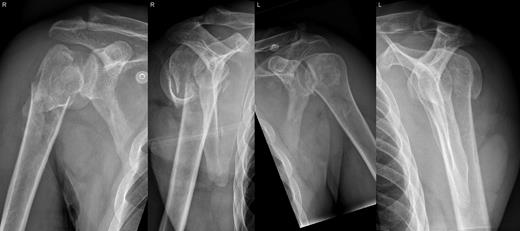

A 48-year-old patient was referred to a level I trauma center after the first incidence of an epileptic convulsion. The patient was alert and oriented with retrograde amnesia from the time of convulsion. Peripheral neurology was normal. The X-rays showed bilateral posterior shoulder dislocation with fractures of both humeral heads (Fig. 1). A CT of the head and both shoulders was performed to exclude intracerebral pathology and to achieve better demonstration of the shoulder fractures (Fig. 2). According to the AO fracture classification, he had a 11-C3.1 fracture on the left side and a 11-C3.3 fracture on the right side. The right side fracture was treated with a cementless hemiarthroplasty (OrTra®, Zimmer, Germany), while an open reduction and internal fixation (ORIF) with an angular stable plate (Philos®, Synthes, Germany) was performed on the left. Despite the high incidence for humeral head necrosis after ORIF in this fracture type, this option was chosen based on the young age of the patient. Postoperative X-rays and CT showed adequate positions of the implants (Fig. 3). The shoulders were immobilized in Gilchrist bandages followed by passive mobilization for the first 6 weeks by physiotherapy with a limitation for abduction and anteversion to 90°. There were no complications intraoperatively or in the first postoperative time. Patient was discharged after 8 days. Antiepileptic therapy was initiated with 5 mg clobazam and subsequent increasing doses over the following weeks. There were no more signs of epilepsy in the follow-up. A CT 4 months after operation showed dislocation of a fragment on the left side which was subsequently resected. At the 1-year postoperative review, the patient showed impingement of the left shoulder with abduction limited to 50° by both the plate and an osteophyte. Radiological assessment revealed signs of necrosis of the head. The plate was removed and the osteophyte resected. Eighteen months after injury, the left shoulder showed progressive avascular osetonecrosis of the head (Fig. 4) and after plate removal an inversed prosthetic replacement had to be performed (Fig. 5). At the last follow-up 3 years after injury, the patient was free of pain with a bilateral range of motion of 90° abduction and elevation.